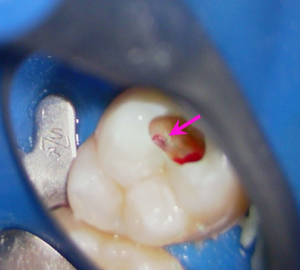

下の写真は虫歯を全部除去した状態です。矢印の部分が歯の神経が露出している部分で、出血があります。神経はピンク色で血管に富みよい状態でした。

治療中のマイクロスコープでの写真です。

神経に穴が開いてしまっている部分を封鎖するためにMTAセメントを用いました。矢印の白色のものがMTAセメントです。

MTAセメントは歯の神経を細菌から保護する作用があります。